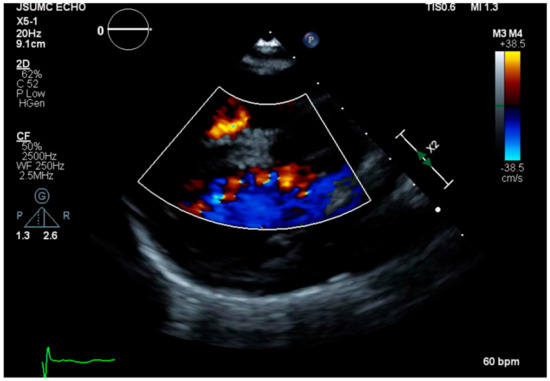

2. Case Presentation